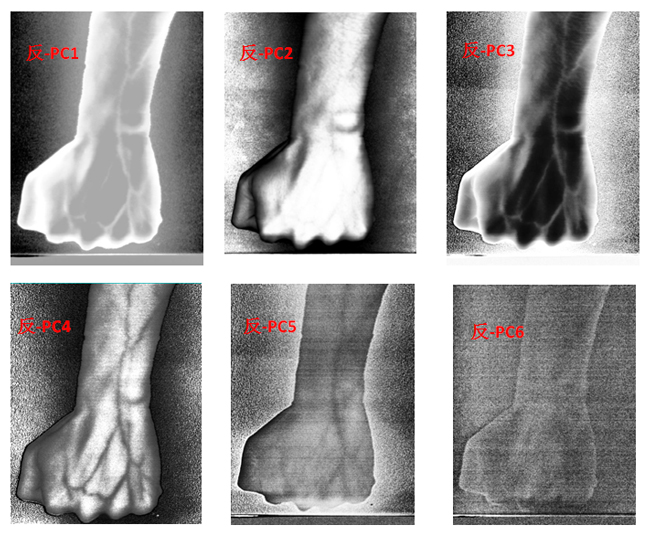

為了客觀地識別手臂上的靜脈,對經(jīng)預(yù)處理后的高光譜數(shù)據(jù)進(jìn)行主成分分析(Principal Component Analysis, PCA),去除波段之間的多余信息、將多波段的圖像信息壓縮到比原波段更有效的少數(shù)幾個轉(zhuǎn)換波段下。圖9為手臂正反面經(jīng)PCA變換后的前6個主成分。

圖9 手臂正反兩面PCA處理后的前6個主成分

為了更客觀真實地識別出手臂靜脈,根據(jù)波段組合的特點,對PCA前六個主成分組合成各種假彩色圖像,如圖10為手臂正面的假彩色合成圖像,圖11為手臂反面的假彩色合成圖像。與灰度圖相比,假彩色合成更能直觀地識別出手臂靜脈。

圖11 手臂反面PCA假彩色合成圖像